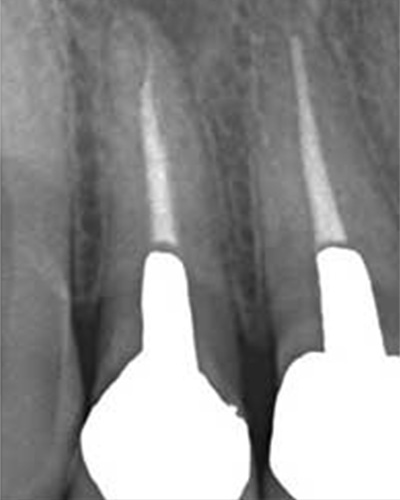

薬が真ん中までしか入っていないため、膿が貯まっている。

ファイルが折れて骨に刺さっている。

奥の歯も薬が入っていない。

実際は2根管だった。

薬が根尖までしっかりはいっていない。

化膿している

小豆大の病巣

ワッテが入っていた 病巣も大きい

突き出たガッタパーチャポイントと大きな病巣

なぜか根管途中から突き出たガッタパーチャポイント